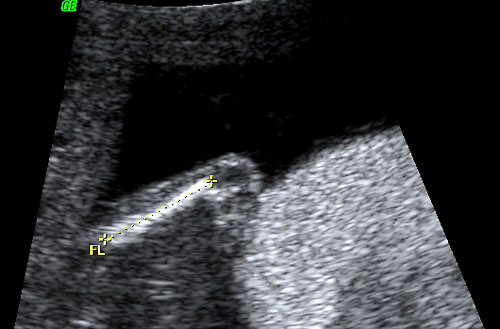

- Short femur/humerus